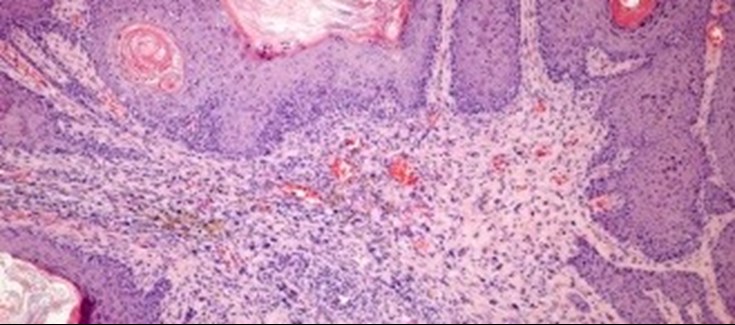

Preparación histológica de una lesión benigna originada en un animal con expresión de IKKb en piel.

IKKb es una proteína con la capacidad de regular la actividad de otras muchas proteínas, importante en la regulación de la inflamación. Trabajos previos de este equipo y de otros habían determinado que IKKb favorece la aparición de tumores de hígado, mama, pulmón y epitelio oral, entre otros. Sin embargo, su rol en el desarrollo de tumores de piel era desconocido hasta el momento. El presente trabajo establece (de forma sorprendente, considerando el papel oncogénico de IKKb en el desarrollo de otros tumores) que IKKb actúa como una proteína supresora de tumores en la piel. IKKb causa en células de piel un aumento en la expresión de importantes proteínas supresoras de tumores, como p53,  p16INK4A y p19ARF. "Nuestros trabajos indican que, para que la función protectora tumoral de IKKb en piel se manifieste,  es necesaria la presencia de p16INK4A y p19ARF, pero p53 es prescindible", afirma Ángel Ramírez coordinador del estudio e investigador del CIBERONC.